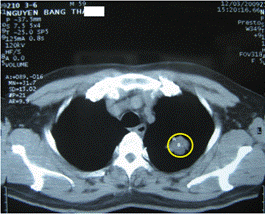

Tại Trung tâm Y học hạt nhân và Ung bướu - Bệnh viện Bạch Mai, khi mới vào viện: bệnh nhân có thể trạng trung bình, cao: 162cm, nặng: 63kg. Sưng, nóng, đỏ các khớp bàn ngón 1 chi dưới 2 bên. Không sờ thấy hạch ngoại vi. Sau đó bệnh nhân được sinh thiết xuyên thành ngực dưới hướng dẫn của CT.

Hình 2: Hình ảnh chụp cắt lớp vi tính (CT) lồng ngực: có khối u phổi trái (trong vòng tròn màu vàng)

Kết quả giải phẫu bệnh: ung thư biểu mô tuyến.